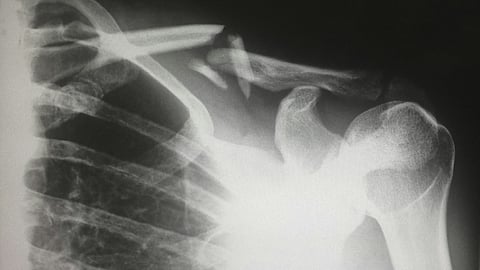

The girl was immediately rushed to Sarvodaya Hospital, where doctors reported she suffered multiple internal injuries, leaving her in critical condition. The entire incident was captured on surveillance cameras, and the footage has since gone viral on various social media platforms, sparking widespread concern.